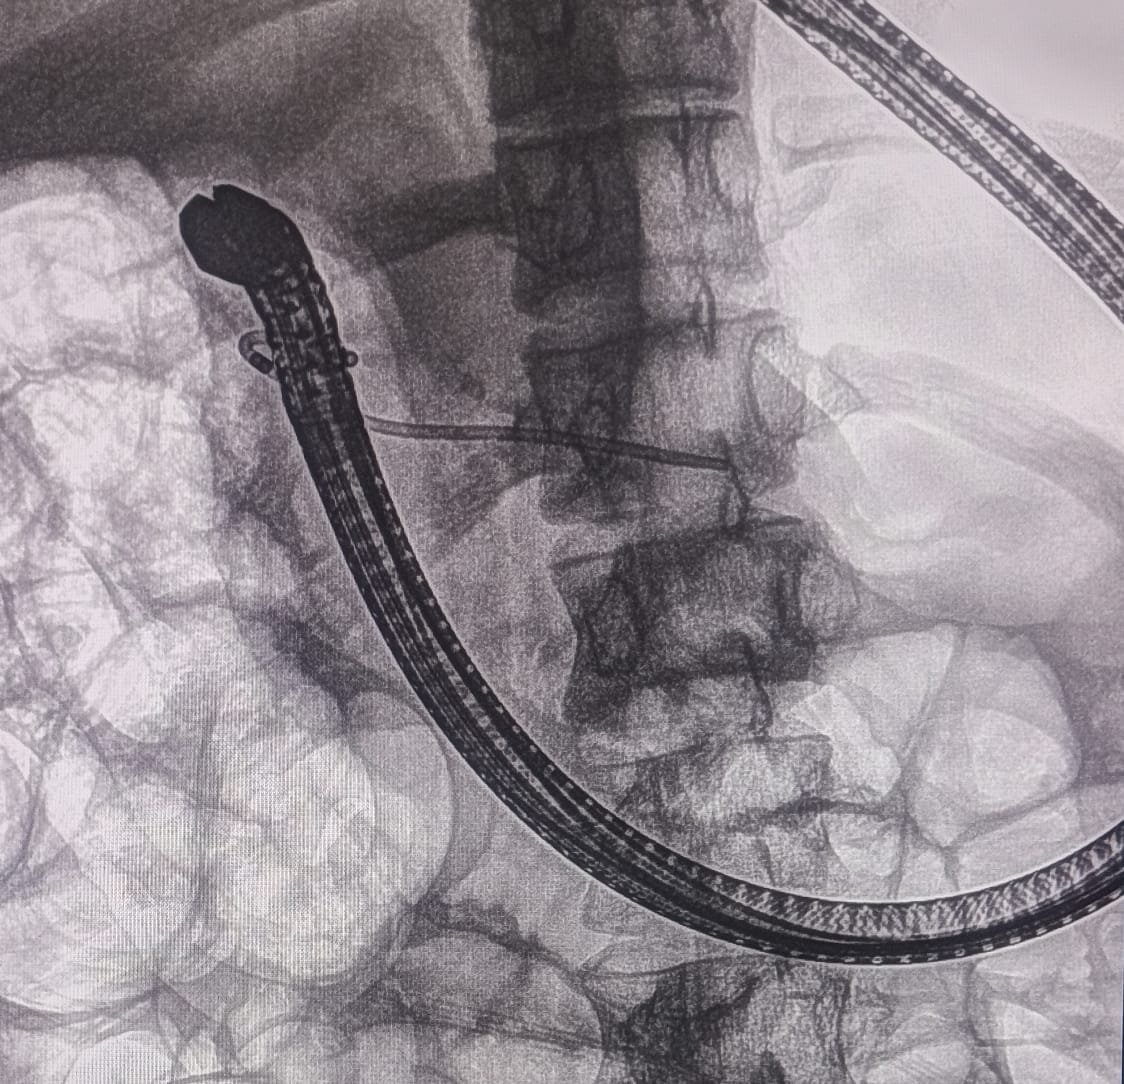

EUS Pancreatogastrostomy Procedure

EUS-guided Pancreatogastrostomy with Stent Placement

EUS Pancreatogastrostomy was successfully performed. The pancreatic duct was identified and punctured under EUS guidance. A wire was placed into the PD, and the tract was dilated with a 6Fr cystotome. A 10mm x 60mm fully covered metallic SEMS was placed.

A plastic stent was placed inside the metallic stent to stabilize and prevent migration of the metallic stent.